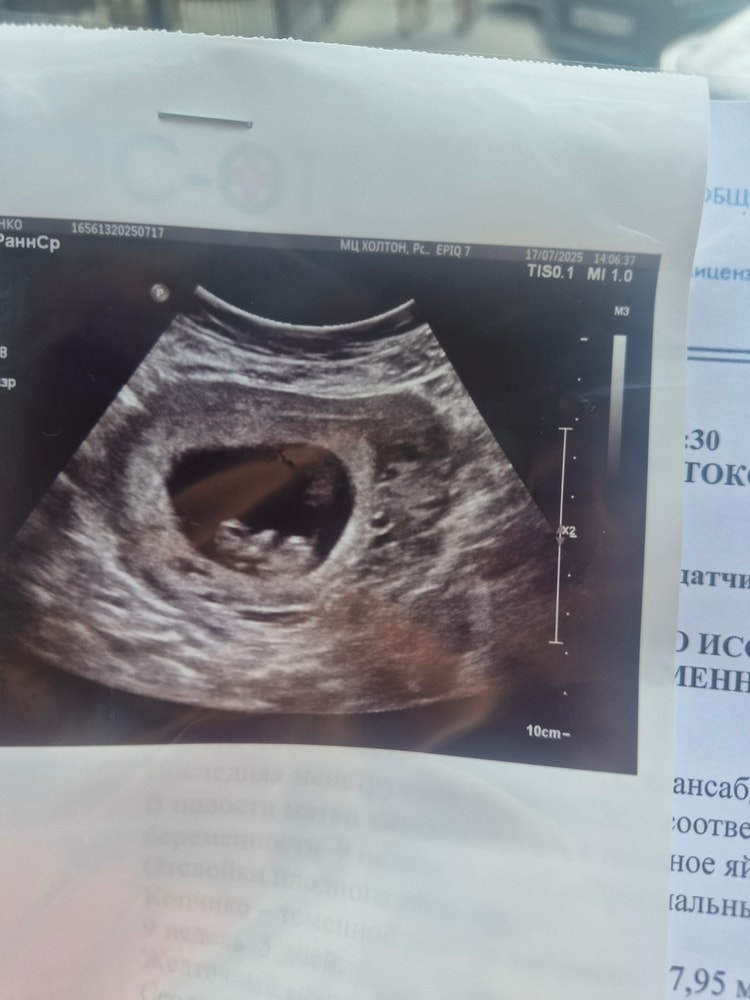

Сегодня на сроке 20.1 прошла 2 ой скрининг в 17 роддоме. Все хорошо у малыша, все на месте. Примерный вес 348 грамм. Соответствует сроку. Единственное, не посмотрели маточные артерии, мне казалось их тоже смотрят, но сказали, что нет

Вот и прошёл первый скрининг. Делала на сроке 12.6 , малыш был обычно меньше на день -два, но сравнялся, ПДР теперь официально на 12.02🙏.

Делала 06.08. Уже через 2 дня вечером результаты крови и рассчетов были в емиасе. Все риски низкие, надеюсь так и есть🙏.